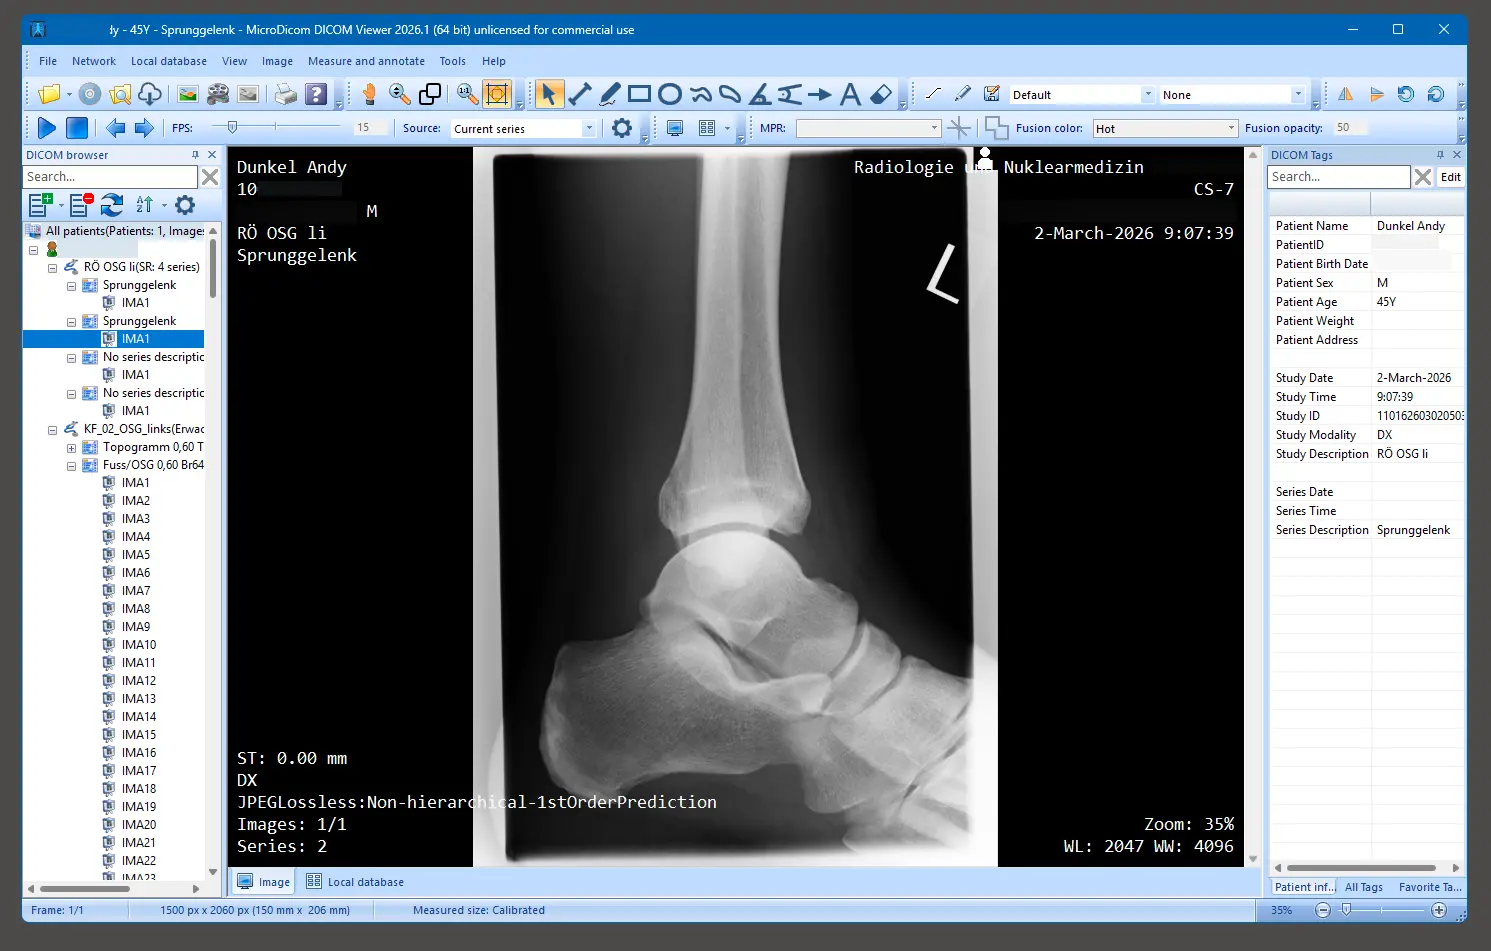

Nach dem Start der Software können wir den Ordner mit unseren Dateien öffnen.

Die Dateien, bzw. Inhalte werden nun angezeigt, auf der linken Seite können wir uns durch die einzelnen Aufnahmen durchklicken.